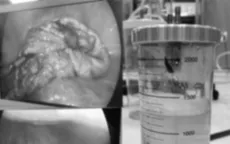

Xử trí thành công u nang buồng trứng hiếm gặp ở bệnh nhi 9 tuổi

VTV.vn - Bệnh viện Phụ Sản Hà Nội vừa nội soi bảo tồn buồng trứng thành công cho bệnh nhi 9 tuổi có khối u dạng nang bì kích thước lớn, nguy cơ ảnh hưởng khả năng sinh sản.